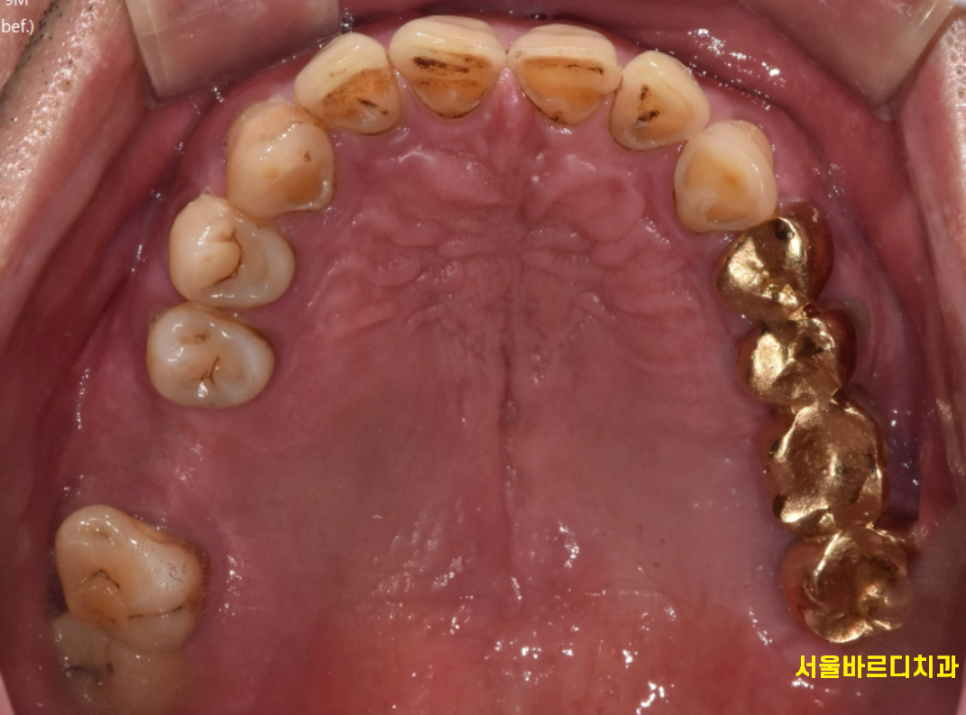

거울로 보이는 화면들

이렇게 생겼을텐데요

지난 시간 설명드린 정지성 우식도 보이고

이를 씌운 치아도 확인이 되네요~~

겉으로 드러난 부분은 보이지만

볼 수 없는 부분도 있죠~?

잇몸 안쪽 부위 확인이 어렵습니다.